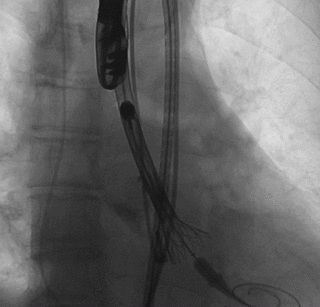

陈灏、冉擘力教授团队术前总结了该病例特点:此病例为type1型二叶瓣,无冠窦钙化非常严重,L-N融合以增厚为主。瓣环周长84.5mm,环上瓣68.7mm,结合左冠高度、瓣叶长度及窦宽,左冠风险较高,需要“down size”。经过反复评估和研讨后,考虑冠脉风险,使用国内首创的电动可回收输送系统--VitaFlow LibertyTM,会降低风险。监护麻醉,经右侧股动脉行TAVR,选用22mm球囊预扩评估冠脉风险,植入VitaFlow24瓣膜。

术中操作

球囊预扩,确认冠脉风险

瓣膜释放至1/2

球囊后扩